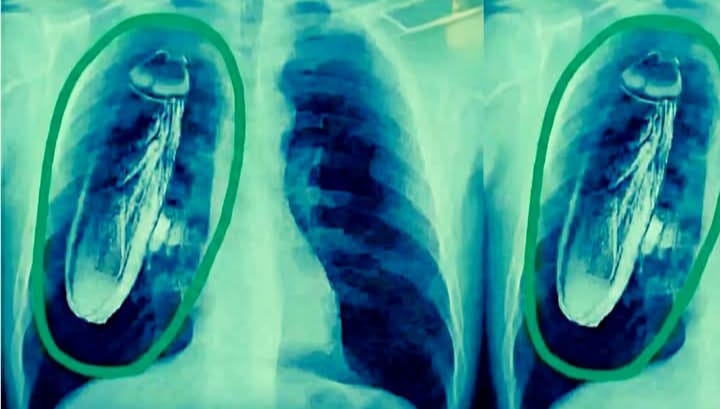

A tourist from Singapore complained of chest pain when his X-ray was taken in Baddi. The X-ray report revealed a cockroach.

बद्दी मे आए आज सिंगापुर के एक पर्यटक को सीने में दर्द महसूस हुआ और इलाज के लिए वहां सरकारी अस्पताल गया। डॉक्टर ने अपने कुछ टेस्ट पर एक्स-रे किया और कहा कि तुरंत सिंगापुर वापस इलाज के लिए चले जाओ क्योंकि उसके सीने में जिंदा तिलचट्टे हैं। निर्देशों के साथ, आपको अपने फेफड़ों के आपातकालीन ऑपरेशन से गुजरना पड़ सकता है।

मरीज अचानक हाथ-पैरों में गिर गया और जल्दी में सिंगापुर लौट आया और एयरपोर्ट से सीधे अस्पताल चला गया। डॉक्टर ने जांच करने के बाद उसे बताया कि कॉकरोच उसकी छाती में नहीं बल्कि बद्दी के एक अस्पताल की एक्सरे मशीन के अंदर था। 😃😃